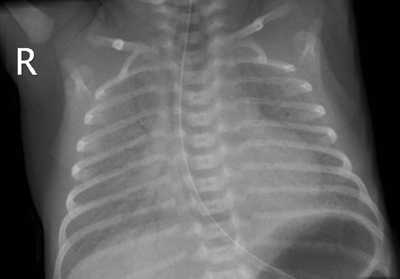

| Синдром дыхательных расстройств | Возникает из-за нарушения образования сурфактанта.

Признаки:

Иногда развивается тяжелая дыхательная недостаточность. |

Рентгенологическая картина легких |

- В случае развития респираторных нарушений показана рентгенография грудной клетки.

Рентгенологическая картина легких